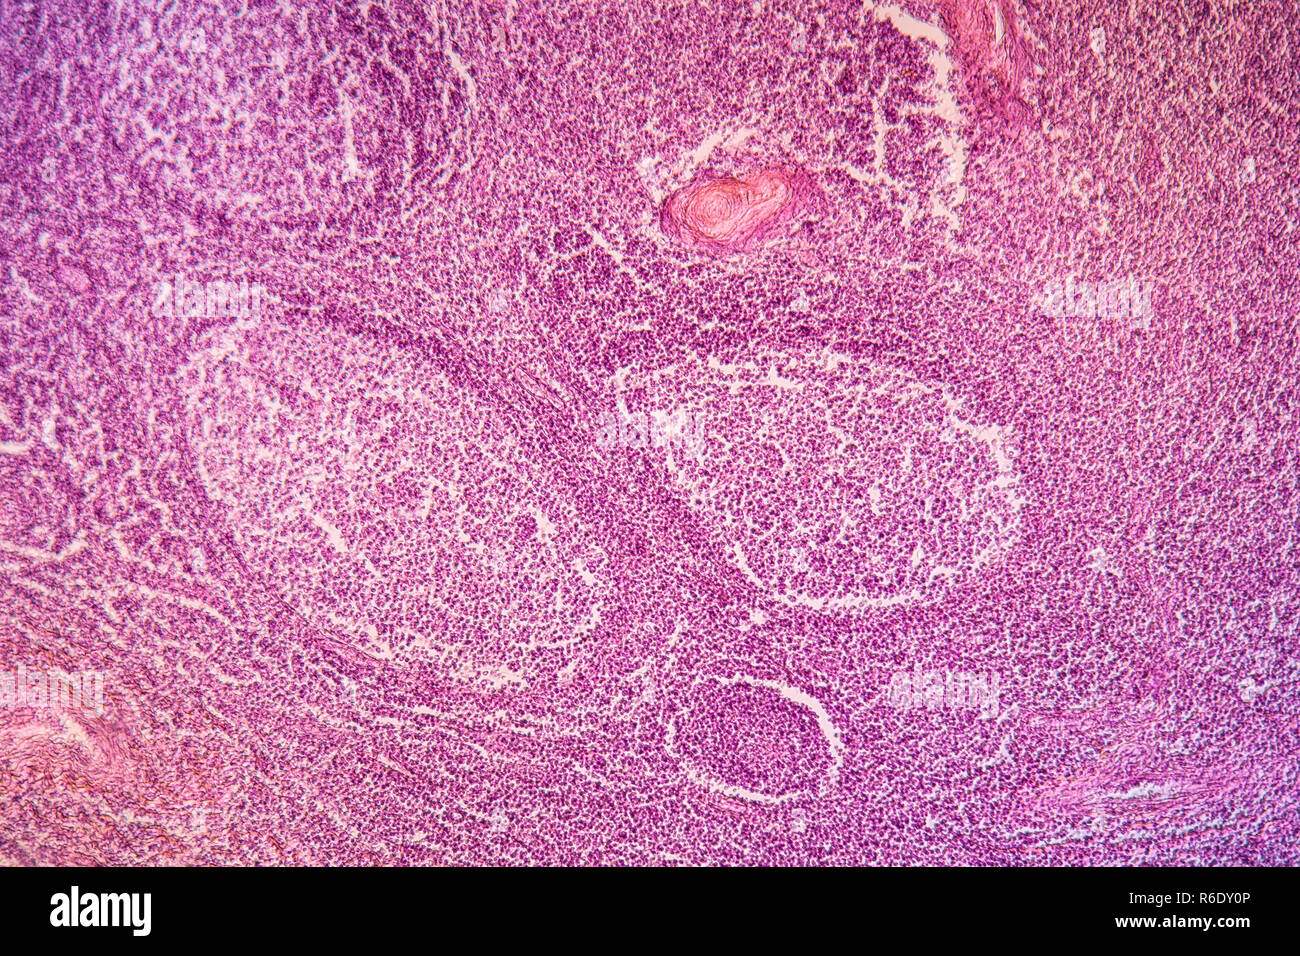

Mandelentzündung krankes Gewebe 100x Stockfotohttps://www.alamy.de/image-license-details/?v=1https://www.alamy.de/mandelentzundung-krankes-gewebe-100x-image227729286.html

Mandelentzündung krankes Gewebe 100x Stockfotohttps://www.alamy.de/image-license-details/?v=1https://www.alamy.de/mandelentzundung-krankes-gewebe-100x-image227729286.htmlRFR6DY0P–Mandelentzündung krankes Gewebe 100x